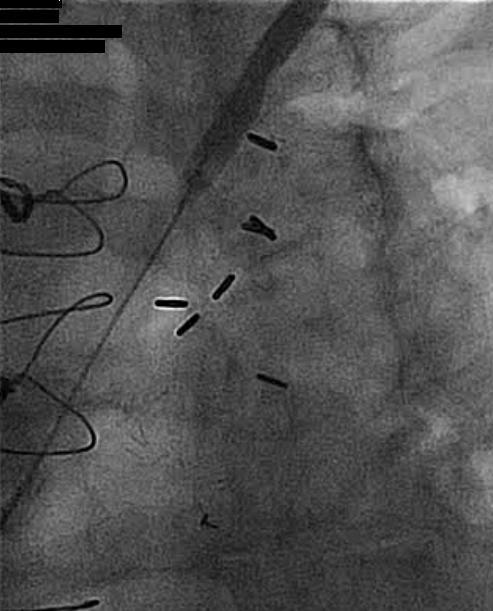

Successful Subclavian Intervention – Pictorial

For illustrative purposes, Figures 4-6 show successful stent placement in a patient with left subclavian stenosis.